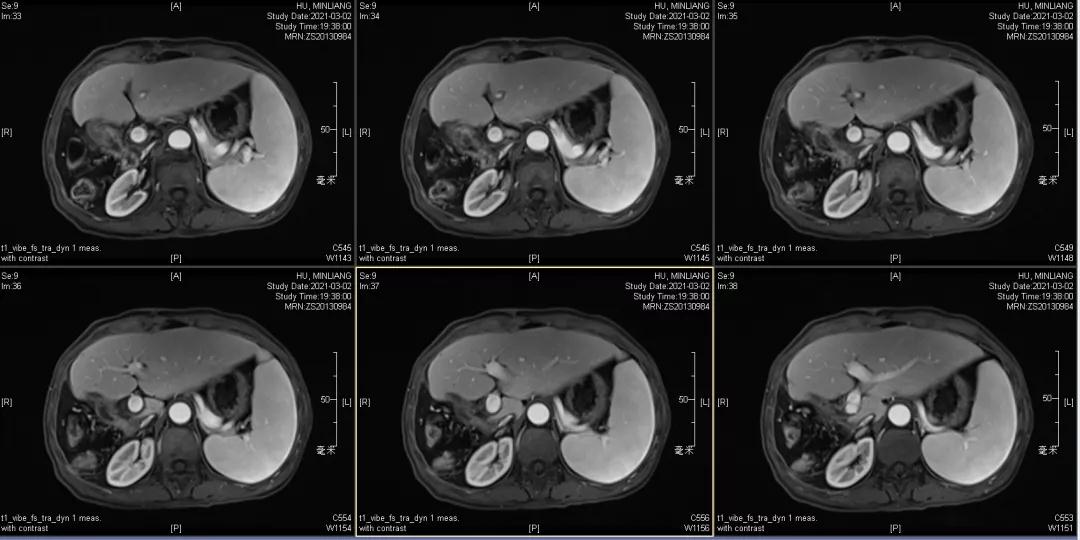

用药6个月后:肝脏病灶明显缩小,子灶消失,仅有少量动脉期强化;肺转移单个持续缩小稳定,PET CT活性弱;HBV DNA 转阴;可考虑转化切除。

2021-2-1 手术切除:右半肝切除术+胆囊切除

术后病理:病理学CR

术后1月复查:磁共振肝内未见肿瘤复发,肺部单个肿瘤稳定。

术后末次随访2021年12月6日,肝内未见明显病灶,肺部病灶稳定1.3cm。